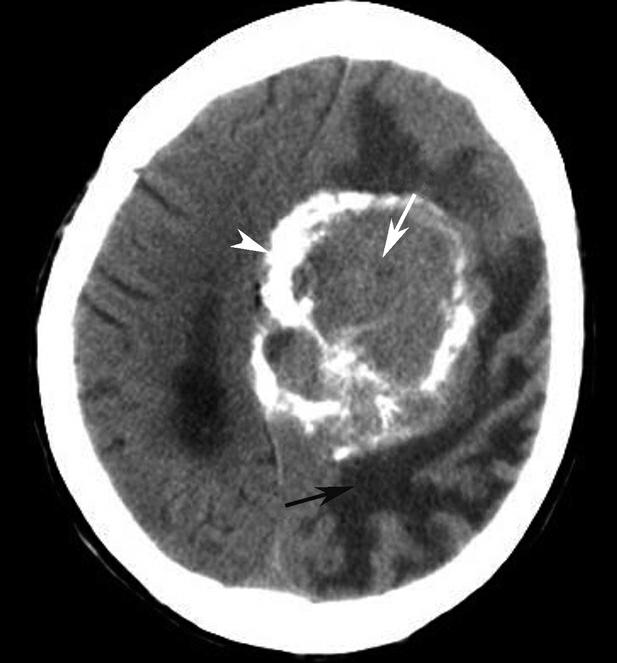

破裂孔、卵圆孔、棘孔及斜坡等均为重要的解剖结构,临床常见疾病如鼻咽癌常侵犯上述结构(图1-2-3)。颈静脉孔区较常见的肿瘤为颈静脉球瘤,常伴有颈静脉孔及其邻近骨质的破坏(图1-2-4)。

图1-2-4 右侧颈静脉球瘤

A.横断面(骨窗);B.横断面

右侧颈静脉孔区不规则骨质破坏(箭),局部见软组织肿块(☆)